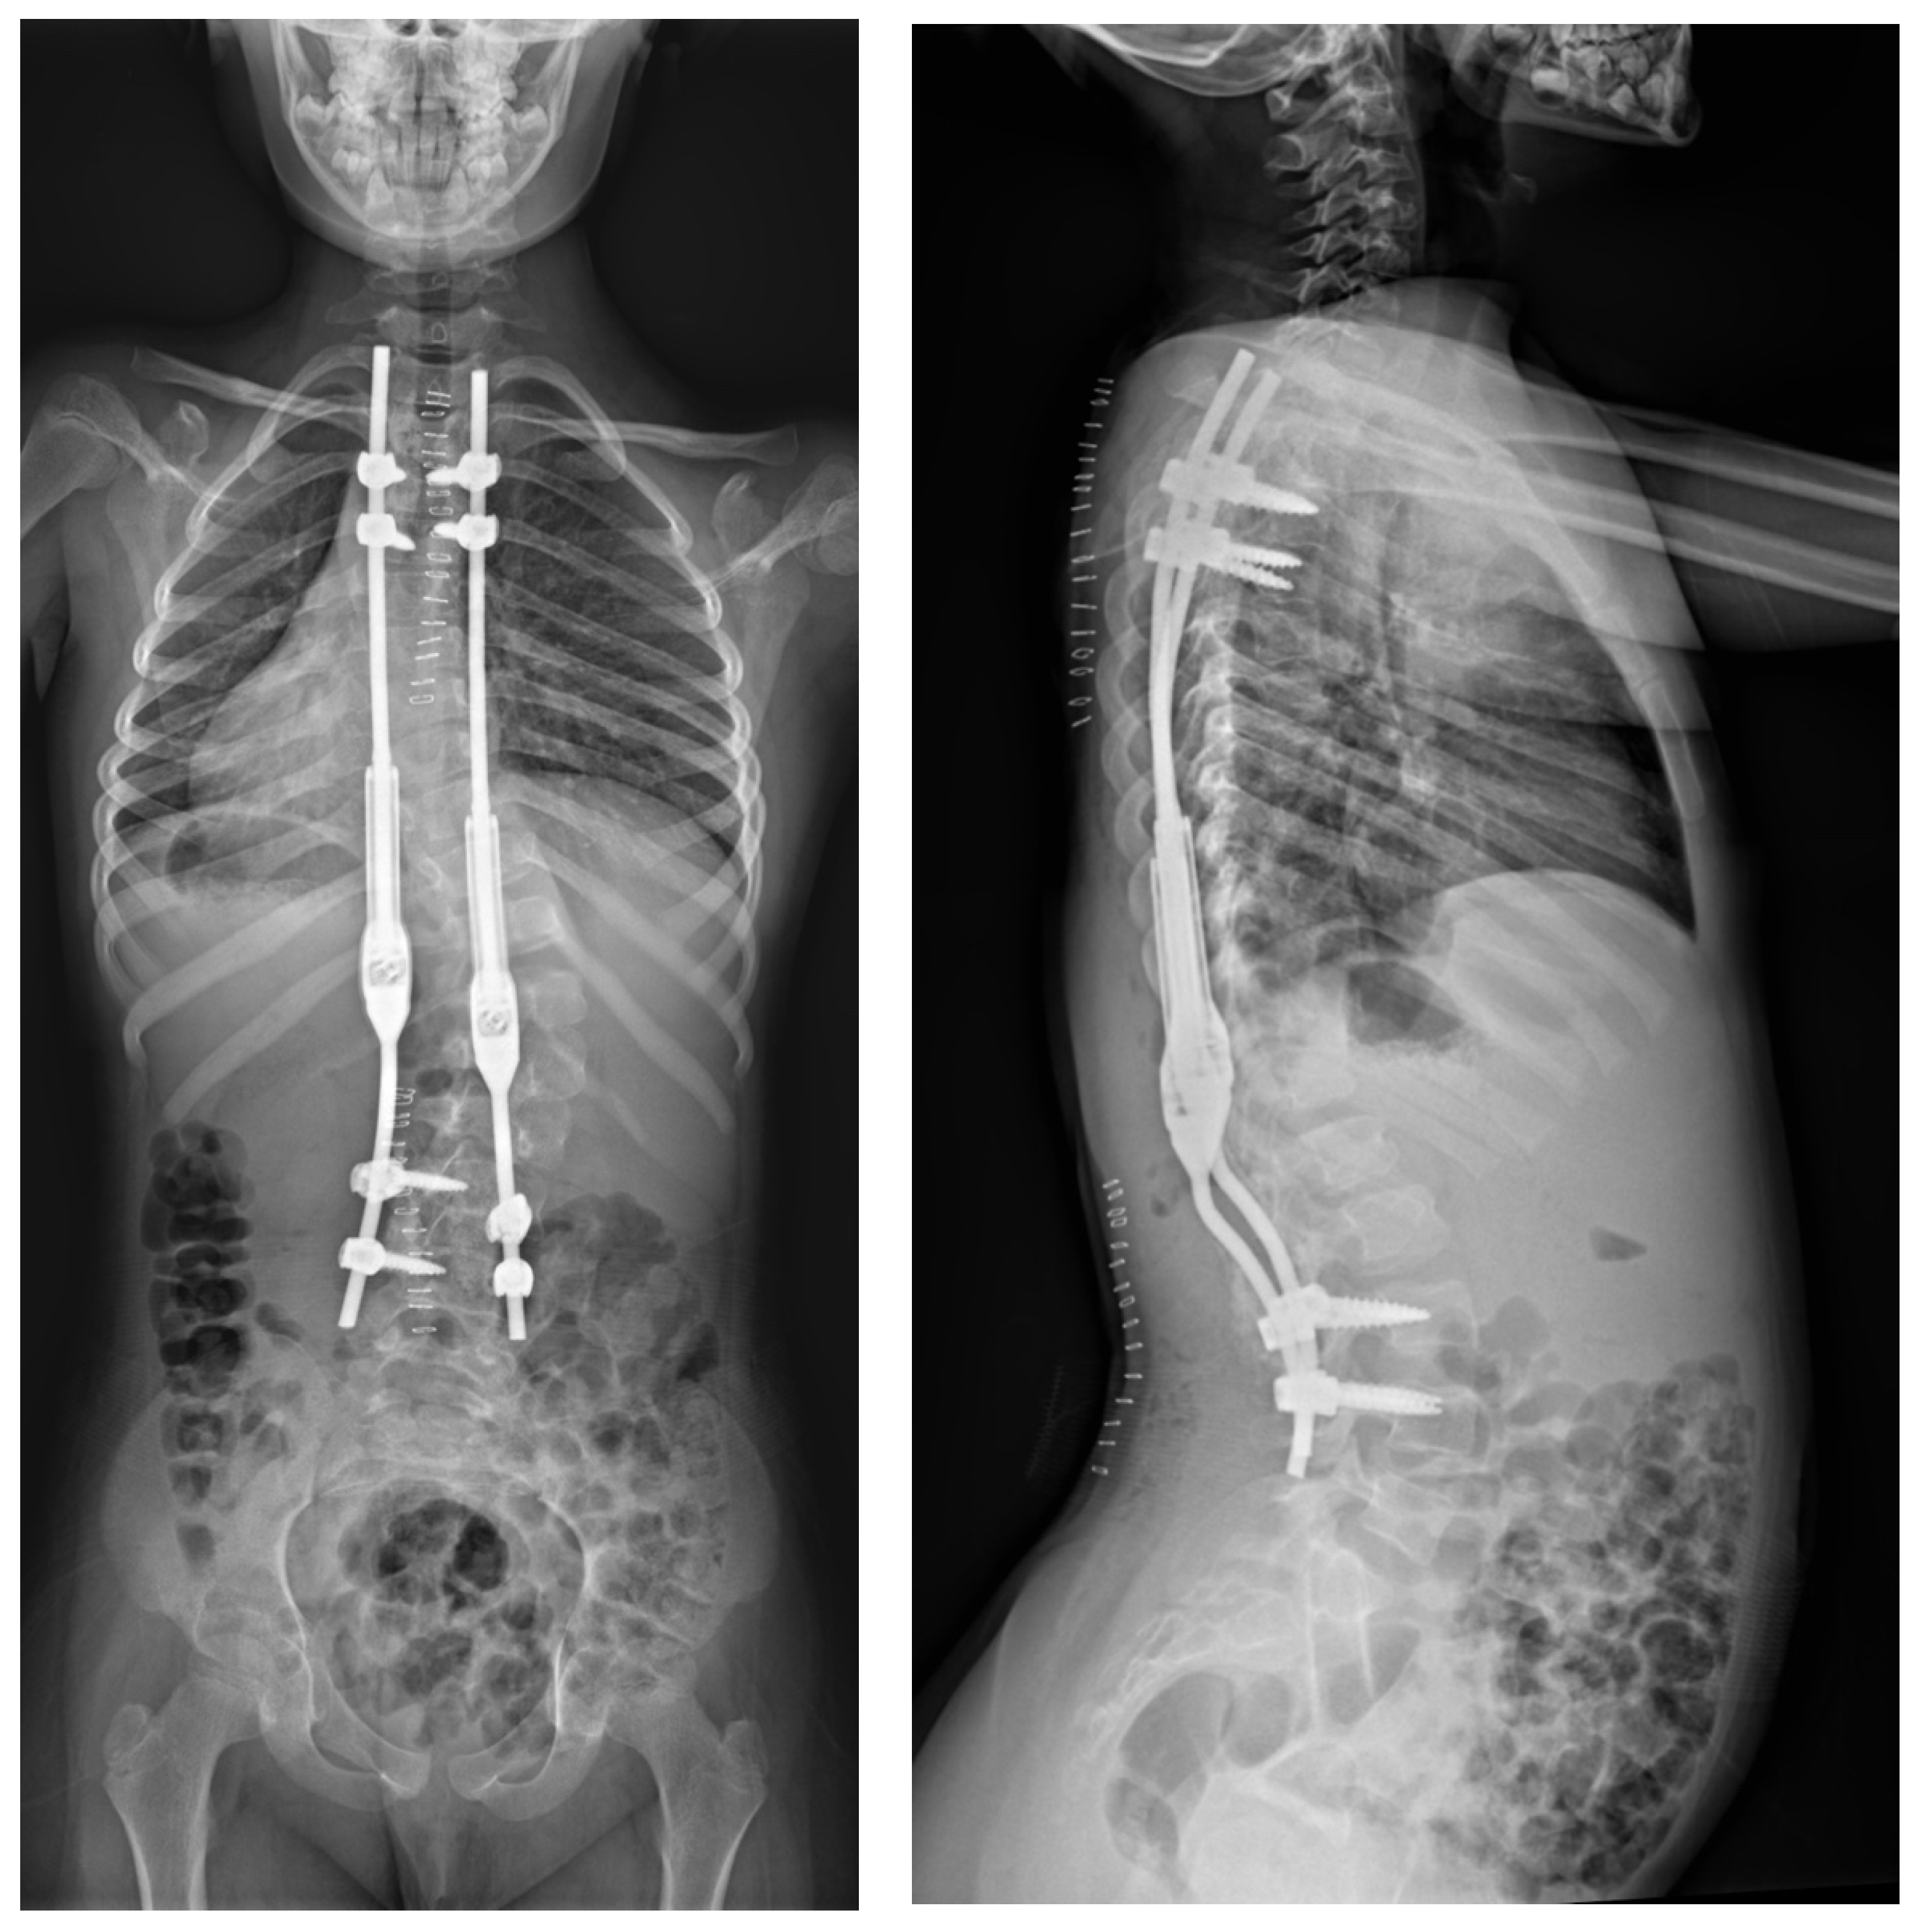

2.2. Example of Early-Onset Idiopathic Scoliosis

2.3. Example of Congenital Kyphosis